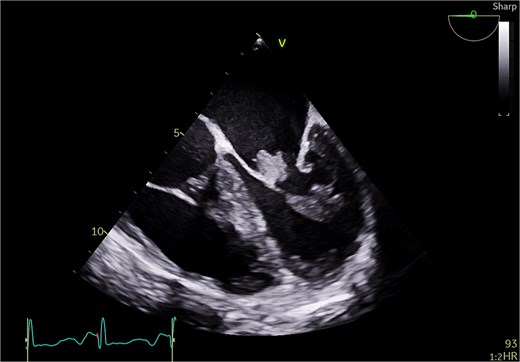

A 51-year-old woman with history of hypertension, hyperlipidemia, diabetes mellitus type II, previous ablation for supra ventricular tachycardia with implantation of loop recorder and sleeve gastrectomy for obesity was referred for surgical evaluation of MR. She was non-smoker with positive family history of ischemic heart disease affecting her mother. She was investigated for recurrent strokes with left sided paresthesia in 2022 and right sided paresthesia with dysarthria in 2024. She had dyspnea on minimal exertion and lower limb edema but no hemoptysis. She had one miscarriage previously with no history of deep vein thrombosis or pulmonary embolism. She had no history of myalgia, arthralgia, and no photosensitivity. Transthoracic echocardiography (TTE) showed pulmonary hypertension with moderate tricuspid regurgitation (TR) and moderate to severe MR and severe mitral stenosis (MS). The appearance was suggestive of rheumatic disease (Fig. 1). Trans esophageal echocardiography (TEE) showed severely dilated left atrium (LA) with no thrombus. Mitral valve with thickened with tethered posterior leaflet with mean gradient (MG) of 13 mmHg. Severe MS and moderate MR with large mass attached to the posterior scallops (Fig. 2) measuring 20 × 15 mm (likely thrombus). Ejection fraction was 55%. She was in sinus rhythm persistently and afebrile. Coronary angiography was normal. She was commenced on oral anticoagulation (Warfarin) for the possible thrombus, and she was reluctant for surgery. Her blood work was normal including normal complete blood count and renal, liver, and thyroid profile with therapeutic international normalized ratio (INR). Blood cultures were negative for growth. She was seen by haematology and work up revealed APS with a recommendation for lifelong warfarin. Patient subsequently accepted surgery.

Transthoracic echo appearance of mitral valve with mass attached to posterior leaflet (apical 4 chamber view).